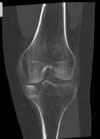

Fratura do platô tibial lateral - Schatzker tipo 2 (traço de fratura + depressão do plato lateral).